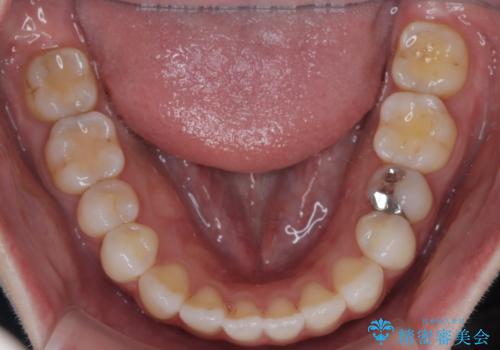

【インビザライン】がたつきをなおしたい

- 上下の前歯の凸凹が気になり、来院されました。

インビザラインで綺麗に仕上がり、満足していただきました。